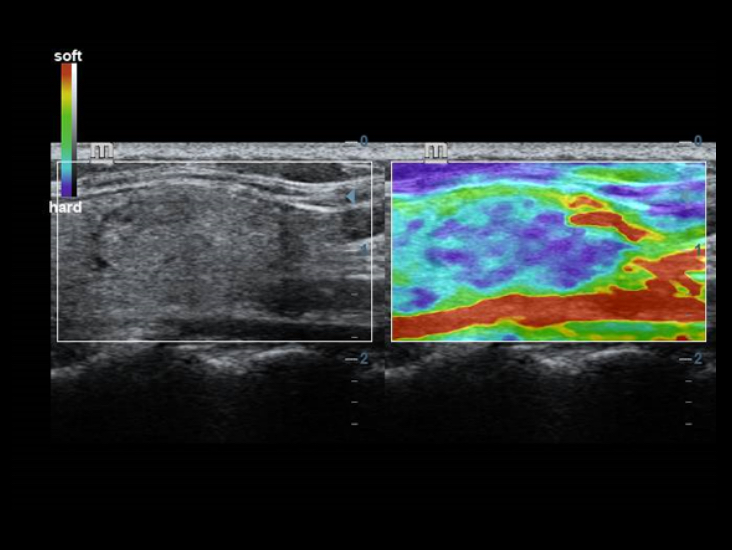

Geleneksel d?nÞ?tÞrÞcÞler ile kar??la?t?r?ld???nda ComboWave d?nÞ?tÞrÞcÞlerin, akustik spektrumu ?nemli ?l?Þde optimize etmek ve akustik empedans? azaltmak i?in yeni bir kompozit piezoelektrik materyal tÞrÞnÞ kulland?klar? g?rÞlÞr. Mindray'in benzersiz 3T teknolojisi ile entegre edilen ComboWave lineer d?nÞ?tÞrÞcÞler, tiroid, meme, vaskÞler ve daha fazla alanda yÞksek g?rÞntÞ ??zÞnÞrlÞ?Þ ve tekdÞzeli?i ile ÞstÞn performans? deneyimlemenizi sa?lar.